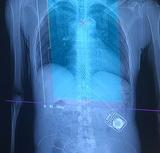

Ahmed Hussein shares his experience living with a spinal cord injury, and the impacts to his daily life regarding blood pressure management with nerve damage. Ahmed participated in the HEMO trial, run by the RESTORE Network at the Hotchkiss Brain Institute. The HEMO trial involved an implant on Ahmed's spinal cord, designed to monitor and modulate blood pressure fluctuations automatically, improving blood pressure symptoms such as hypertension, fainting, flushing, clot risk and more.